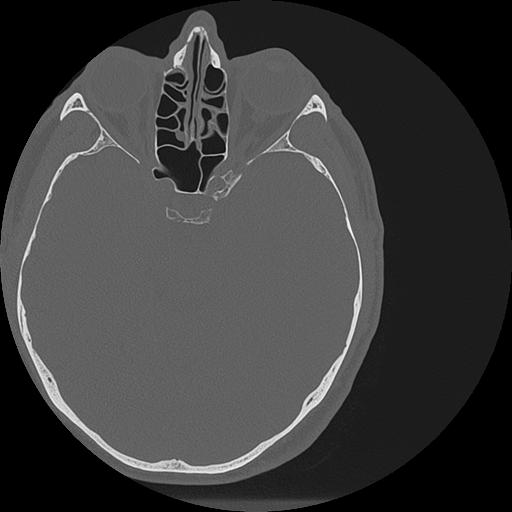

7 HUESO,,Vol,0.5,HUESO,,